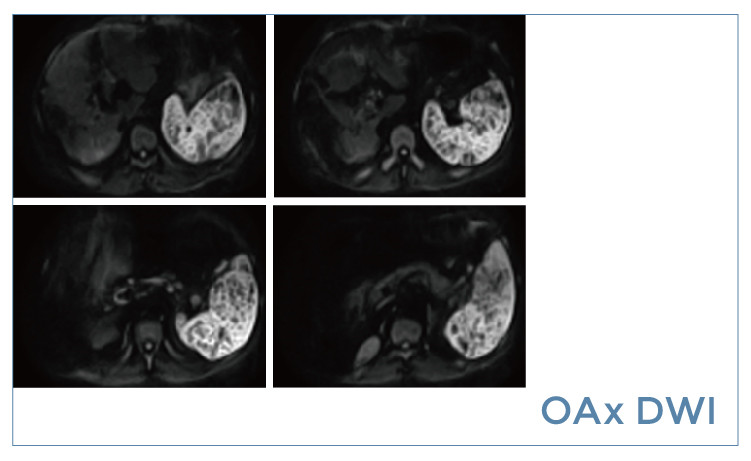

朗润影像档案】磁共振影像病例分享(编号20190517)